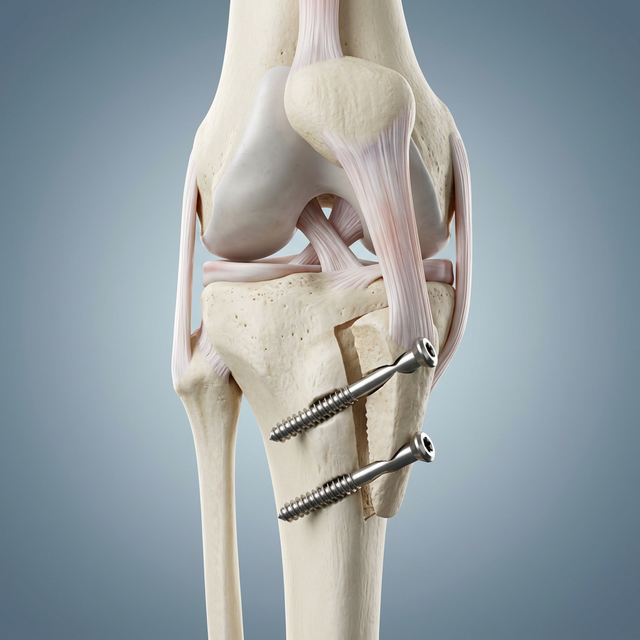

Tibial Tubercle Osteotomy (TTO) is a powerful realignment surgery designed to correct the tracking of the kneecap (patella) by repositioning the tibial tubercle—the bony attachment point of the patellar tendon. For patients whose kneecap is pulled too far outward due to their bone structure, this procedure allows us to shift the tubercle inward (medially) or forward (anteriorly). This takes the pressure off worn cartilage and ensures the patella glides perfectly within its groove, preventing future dislocations and slowing the progression of arthritis.

Carefully detaching the tibial tubercle and shifting it to its new, anatomically correct position.

Internal Fixation

Securing the bone in its new position with two titanium compression screws for permanent stability.